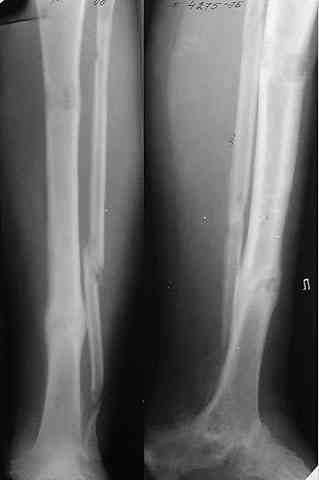

Не адресована другая проблемы - берцово-пяточный блок достигается ценой укорочения конечности на 3-4 см. Поэтому надо предусмотреть что-то для удлинения. У нас в клинике традиционный подход - билокально удлинять большеберцовую кость. Раньше еще и малоберцовую рубили на двух уровнях. Сейчас (спасибо коллегам из форума) пользуемся только

той остеотомией, которая делается для отворачивания кожно-костного лоскута с малоберцовой костью. Фиксируем все это аппаратом (пример в приложении) около 4 мес.

То есть относительно недолго. Про винты поэтому стоит вспомнить, только если опору со стопы хочется снять совсем уж рано. Можно, в принципе, и о штифтовании подумать. Правда, мы пока думаем - они так срастись успевают.